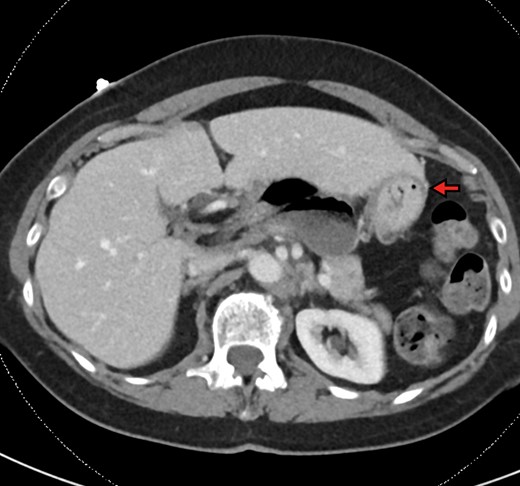

The patient is a 70-year-old woman who presented to the emergency department with acute-onset abdominal pain throughout her epigastrium for approximately 2 hours. The pain was constant and severe, extending across the bilateral upper quadrants. She had experienced pain like this once before within the past year which spontaneously resolved within 4 hours. The patient’s last oral intake was an hour before onset of the pain, and she denied any fevers, chills, nausea or vomiting. She was an otherwise healthy woman who took no medications and had no abdominal surgical history. On admission, vital signs were normal, with a heart rate in the 70’s. Although initially reported as tender by emergency department staff, after pain medication and intravenous fluids, examination by the surgical team revealed resolution of pain and a soft, non-tender abdomen. Lactic acid on presentation was 5.0 mmol/l, and her white blood cell count was 9600 µl−1, with the remainder of her laboratory values within normal limits. She underwent a computed tomography scan which demonstrated herniation of her cecum through the FoW, causing compression of the inferior vena cava (IVC) and portal vein (Figures 1–3).

Axial view demonstrating multiple air-fluid levels posterior to the liver and adjacent to the stomach (red arrow).